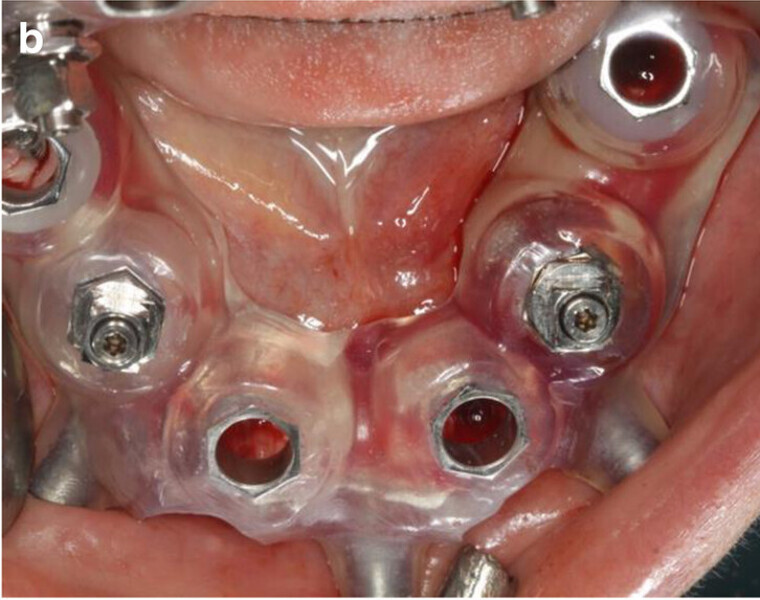

Fig. 9a: Occlusal views of the abutments (a) and of the immediate provisional restoration that were passively bonded in situ (b).

Fig. 9b: Occlusal views of the abutments (a) and of the immediate provisional restoration that were passively bonded in situ (b).